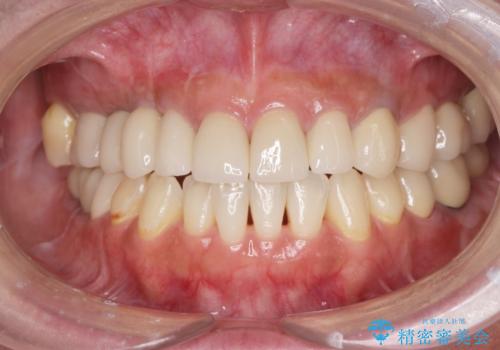

[ 破折し大きく吸収した歯槽骨 ] 他院では難しいと言われたインプラント治療

![[ 破折し大きく吸収した歯槽骨 ] 他院では難しいと言われたインプラント治療の症例 治療後](https://seimitsushinbi.jp/wp/wp-content/uploads/2024/10/7e00d9287463e80cbc3d4b87784b3d86-500x350.jpg?v=1729760167)